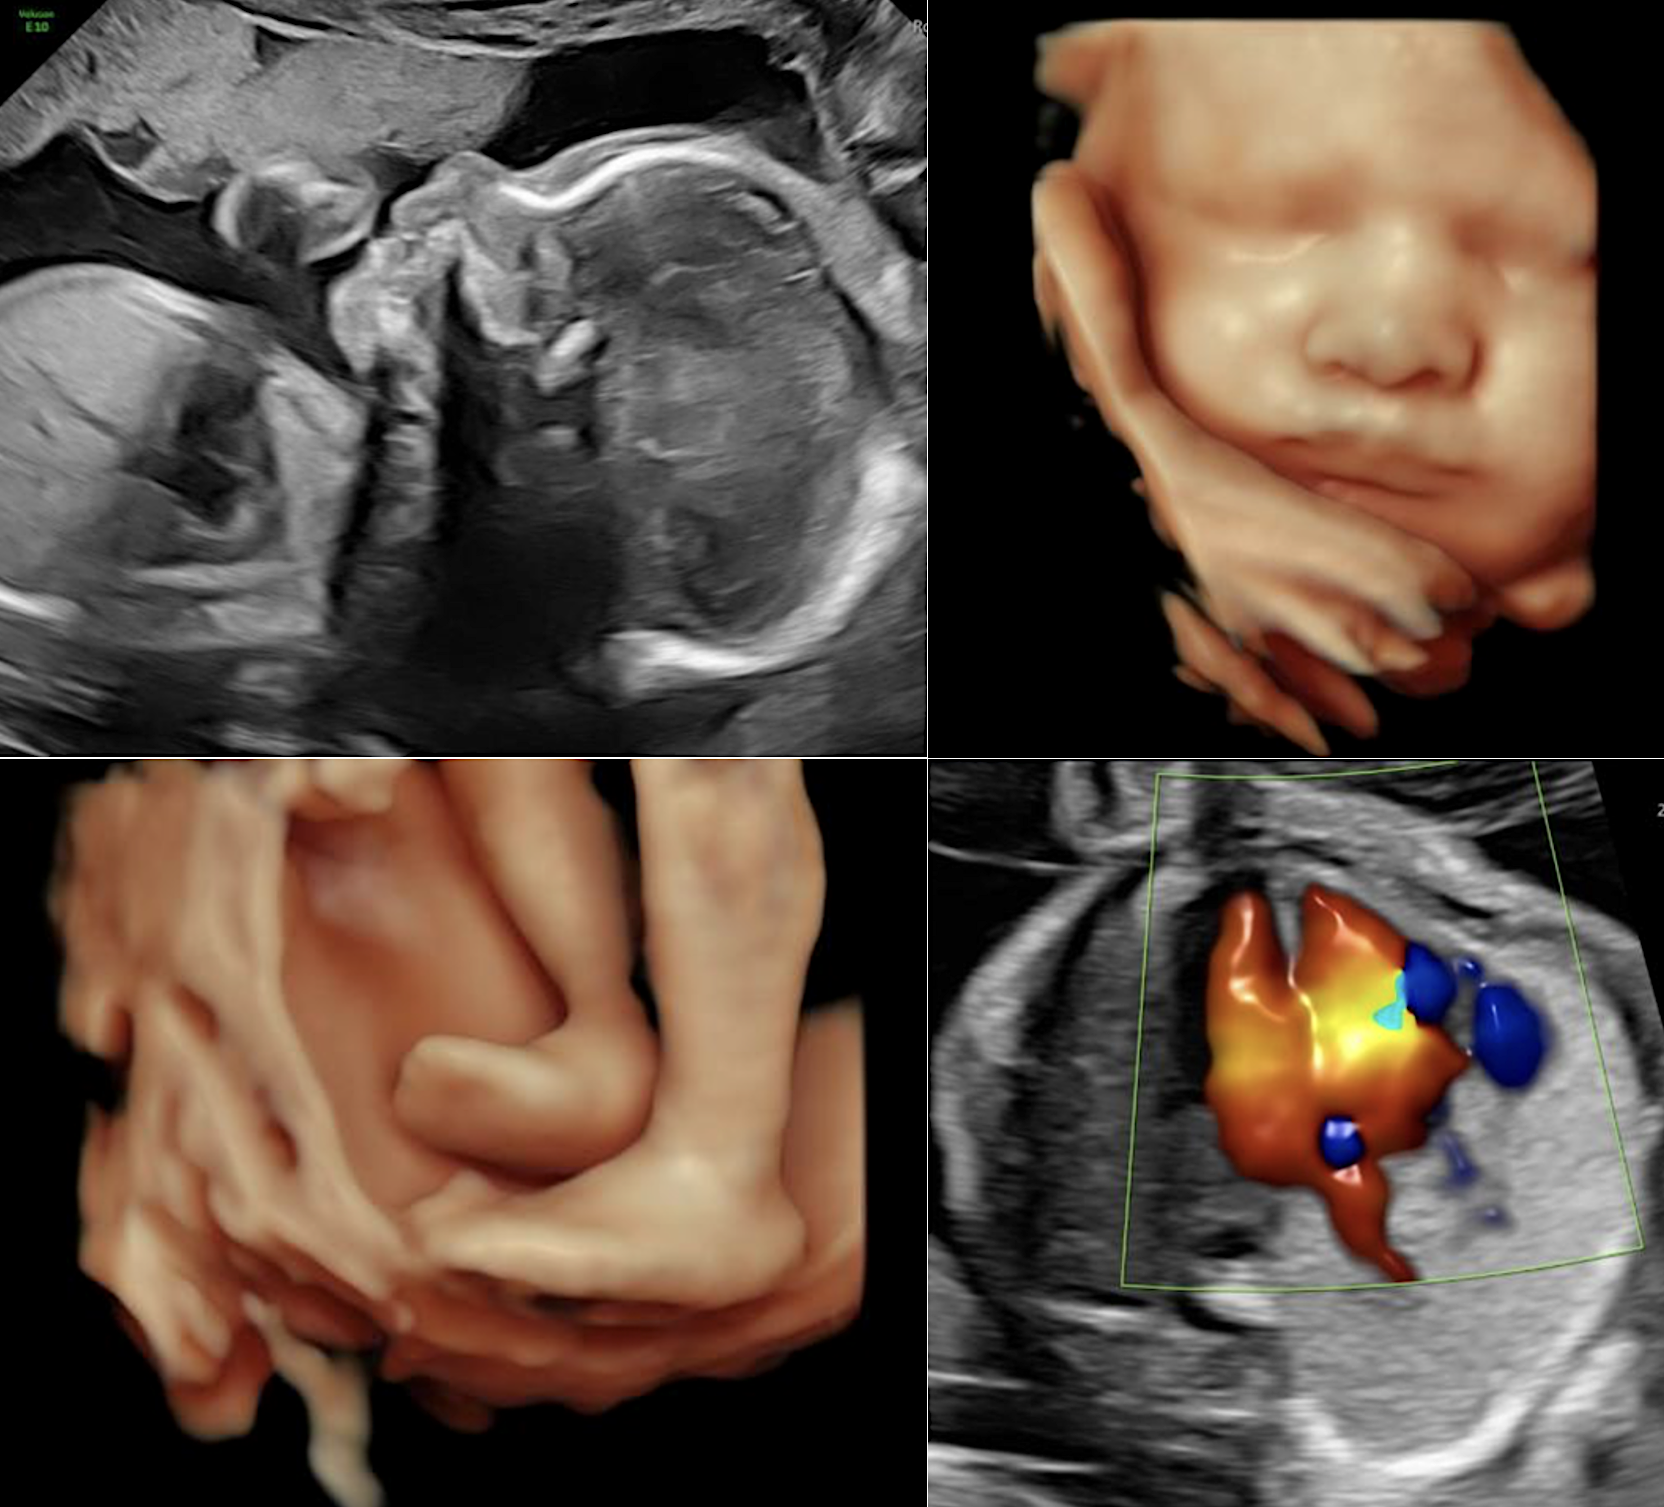

Équipement de dernière génération (Voluson E10) permettant des reconstructions 3D/4D de haute qualité.

L'échographie obstétricale est un examen d'imagerie médicale totalement indolore et sans danger, utilisant les ultrasons pour explorer et interpréter les images du fœtus.